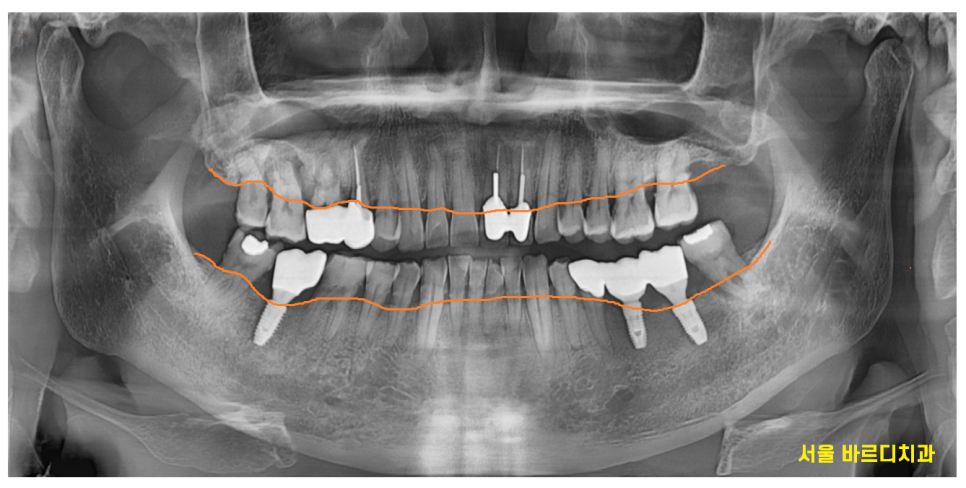

23.07.04

역시나 잇몸뼈가 머리까지 차 있어야하는데

많이 내려가 있는것이 보입니다.

전체 28개의 치아중에서

유독 안좋아보이는 오른쪽 윗니 치아

추가적으로 검사를 해보았는데요.

큰 어금니 2개 상태가 영 ㅠㅠ 별로네요.

잇몸뼈가 많이 내려가다보니

어금니 시림 현상이 발생